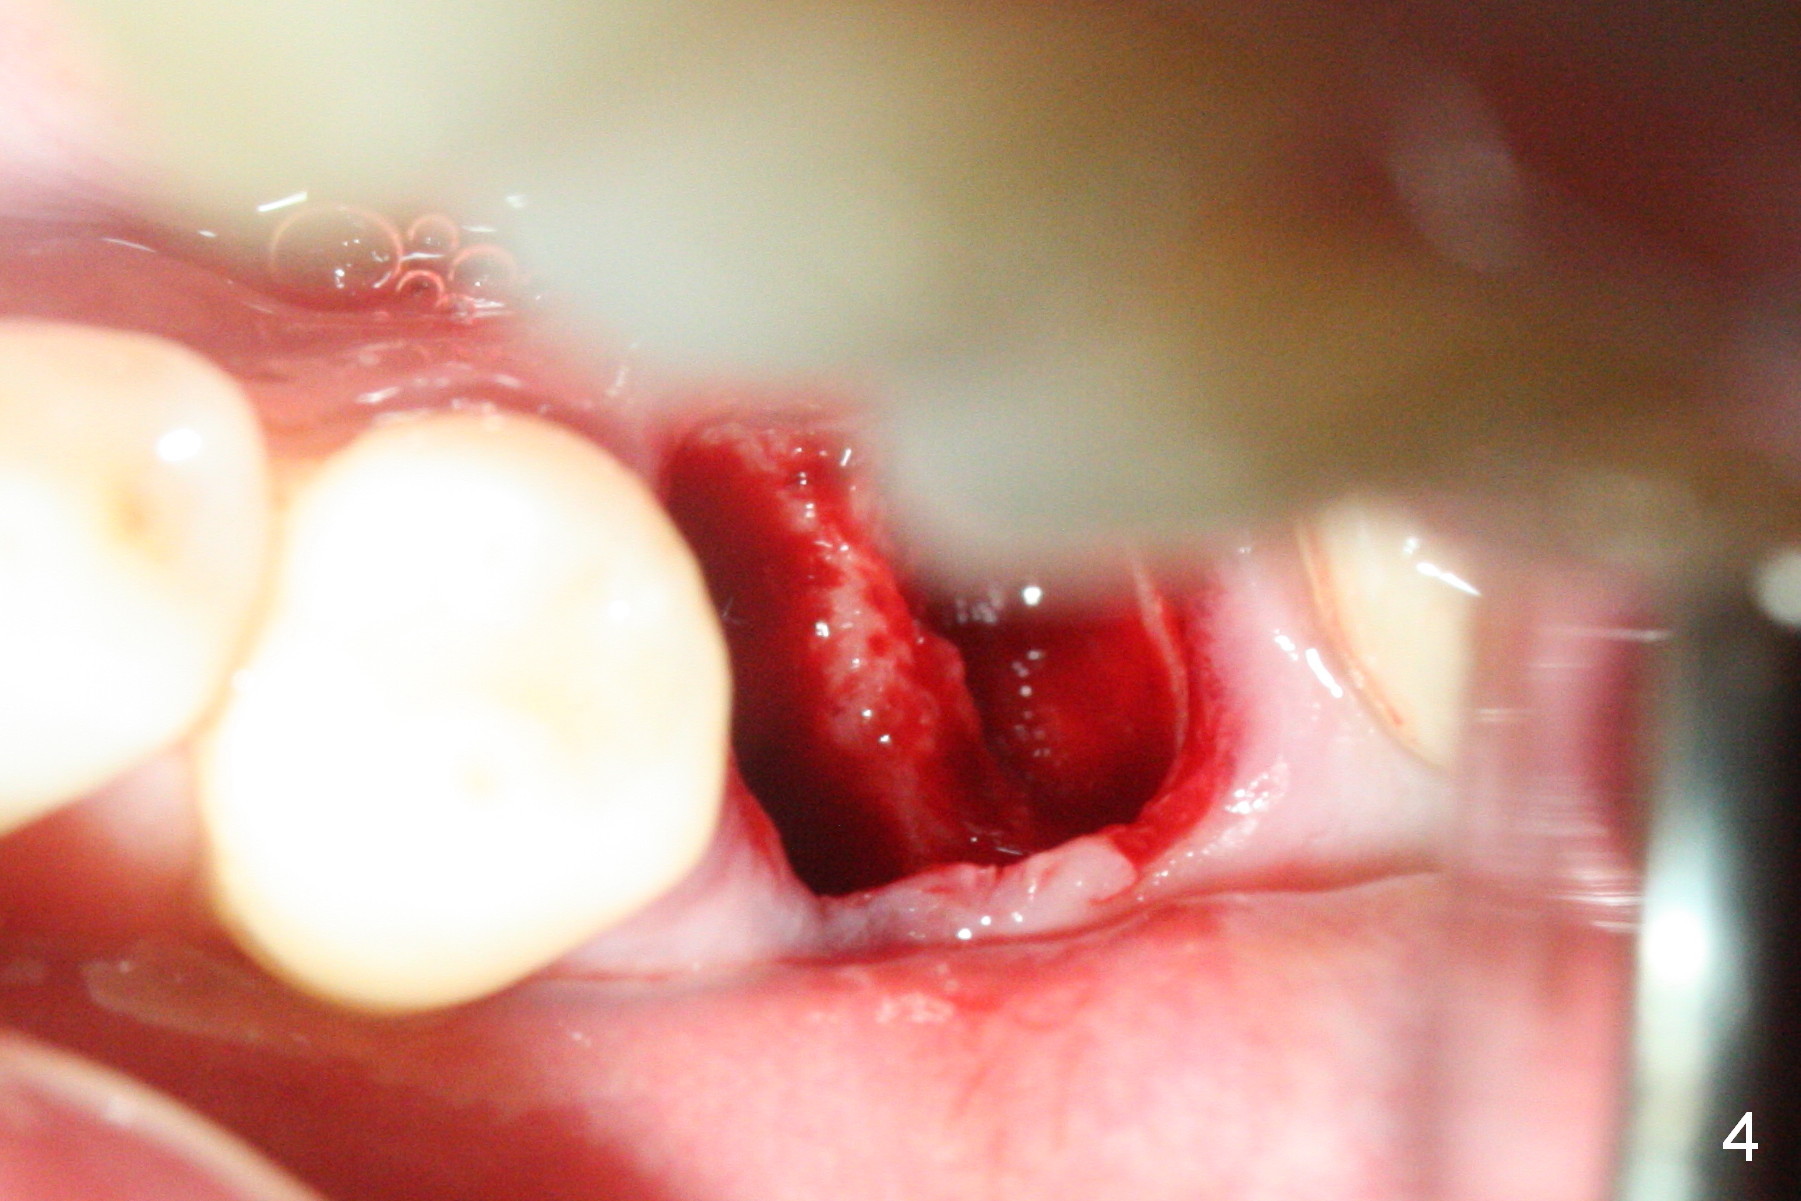

The tooth #19 is easy to get loose, but it cannot be luxated.  After sectioning and extraction (Clindamycin), the septum is found to be thin (Fig.4).  A surgical fissure bur is used to initiate osteotomy, followed by 1.6 mm pilot drill.  It is difficult to use Marking bur (wobbling over the basically pointed septum).  It is impossible to use 4.3 mm Magic Drill (MD, one drill system), since it jumps.  The smallest MD has to be used (2.8 mm).  When the next drill (3.3 mm) is being used for 13 mm with stopper (Fig.5), the patient experiences transient pain.  The depth is suggested from the design in Fig.2.  The thin septum appears not to be a reliable landmark.  When block anesthesia is administered, the initial depth should be shortened.  The drill appears to be close to the Inferior Alveolar Canal (Fig.5).  Then the depth changes to 11 mm with the following drills (3.8 and 4.3).  The mesial and distal walls of the septum are gradually perforated.  A 5x9 mm dummy implant is placed only after using 4.8 mm drill (Fig.6).  The implant appears to be short.  When a longer implant is placed (5x11 mm), it does not easily enter the osteotomy, either sliding into the mesial or distal socket with the implant separating from the implant driver.  It appears that a premount implant is appropriate in this situation.  When the 5x11 mm implant is finally seated with stability, it is 6 mm apical to the gingival margin.  The longest cuff of IBS abutment is 4 mm.  A longer implant is needed (Fig.7, 5x13 mm).  Placement is not easy as mentioned above.  Insertion torque is <20 Ncm when the patient experience a little discomfort.  A 6.5x4(4) mm pair abutment is placed (A), apparently proper for restoration.  Allograft is placed (Fig.8 *) prior to immediate provisional.  The patient complains of bad smell from the site 24 days postop.  When the provisional is removed, the abutment is found to be mobile.  When the latter is removed with local anesthesia, bone graft granules are attached to the socket above the lightly mobile implant (Fig.9).  In fact the latter appears to be stable after a few turns by finger.  A healing screw is placed; the socket is closed with collagen plug and 4-0 Chromic gut sutures (Fig.10).  It appears that a larger implant should have been used to achieve higher torque.  Two months later (3 months postop), the coronal end of the implant is partially exposed.  A 5x4 mm healing abutment is placed.  It appears that the implant is stable.  The implant appears to have osteointegrated 4 months postop (Fig.11).  Impression is taken.